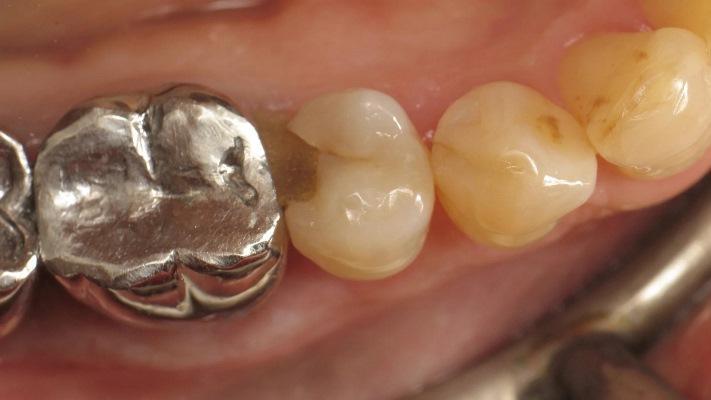

Фото 4: Установка проксимальной матрицы.

Для достижения удовлетворительной анатомии и функциональности необходимо учитывать несколько элементов: препарирование, разделение межзубных промежутков и контурная пластика. Для восстановления проксимальной стенки, разрушенной кариозным поражением, следует использовать матрицу. Как правило, используется металлическая матрица, поскольку она податлива и не прилипает к реставрационному материалу. Высота матрицы имеет решающее значение. Если она будет слишком короткой, пломба будет нарушена, а если она будет слишком длинной, манипуляции будут затруднены из-за десневого сосочка. Разделение межзубных промежутков включает в себя расширение межзубного пространства с помощью клина. Обычно клин изготавливается из дерева или пластика различных размеров. Размер клина имеет решающее значение. Если клин слишком мал, точка контакта будет слишком свободной, но, если клин слишком большой, может возникнуть послеоперационный дискомфорт. Контурная пластика включает в себя определение общей формы проксимальной поверхности зуба. Чтобы прижать матрицу к зубу и придать реставрации естественную форму обычно используется кольцо.